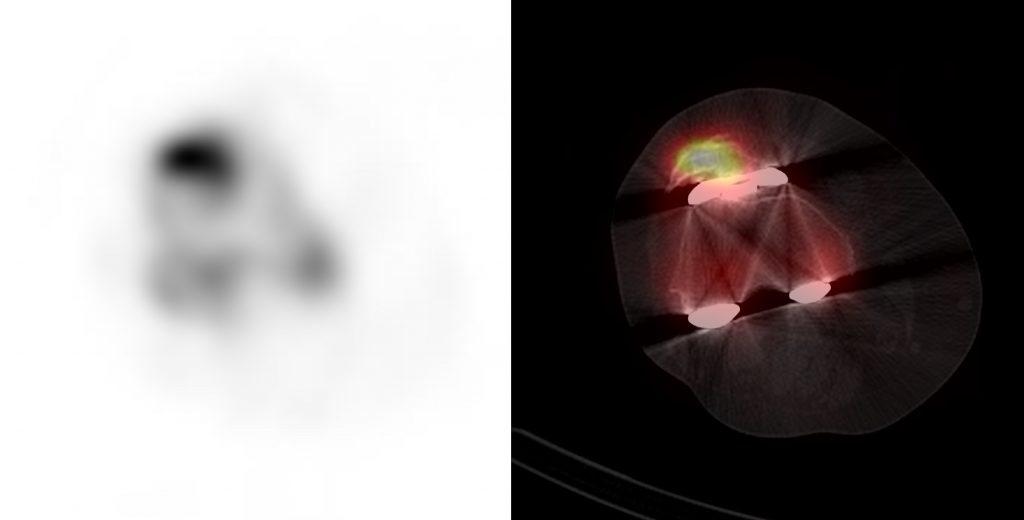

We have recently started performing SPECT-CT during the blood pool phase instead of planar imaging.

Finally, a delayed phase SPECT-CT of both knees is performed. Our CT scans are performed with an extended Hounsfield scale to reduce metallic artefact.

Focal increased uptake seen within the patellar facet is suggestive of patellofemoral degeneration. The position of the femoral component can result in abnormal loading on the patellofemoral joint. Internal rotation of the femoral component can result in loading on the lateral patellar rim. A flexed femoral component can cause increased uptake in the proximal patella due to overstuffing of the patellofemoral joint.

In patients who have undergone resurfacing of the patella, increased uptake around the patella resurfacing can indicate loosening of the prosthesis, infection, or mechanical overstressing.